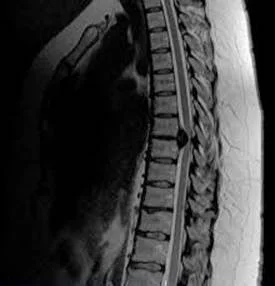

Чому болить в грудях посередині?

Отже, біль в грудях посередині. Захворювання серця, ні? Не завжди. Різні причини, і деякі з них можуть змусити вас затримати дихання від нерозуміння, інші ж просто схопити валер’янку.

- Серце: так, це перше, про що думають. Іноді ваш вірний моторчик дає збій. Міокардит, стенокардія, інфаркт — страшні слова, але їх варто знати.

- М’язи і кістки: іноді біль виникає через пошкодження м’язів чи навіть переломи. Впали на ковзанці, а тепер все болить і ниє? Знайома картина.